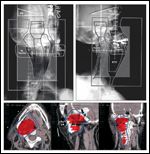

FIGURE 1

Three-Dimensional Treatment Plan

In general, a total dose of 45 Gy delivered over 5 weeks is recommended (Figure 1). However, a schedule of 35 Gy delivered over 3 weeks has also been shown to be effective in a Canadian study.[24] The majority of lesions remain stable in size or show modest regression on radiographic evaluation after the completion of radiotherapy.[ 14,27,40] Paralleling the high rates of local control are diseasespecific survival rates ranging from 65% to 100%, with the majority of series reporting rates of 90% to 100% and overall survival rates of 65% to 100% (Table 1).[1,2,4-39]

With modern treatment planning and appropriate dosing, definitive radiotherapy for paragangliomas should be well tolerated. In the acute setting, patients may experience dermatitis, alopecia, mucositis, epilation, and alterations in taste and saliva along with either otitis externa or media. The potential complications vary according to the radiation technique and site of treatment. At a standard total dose of 45 Gy delivered over 25 fractions, most of these side effects are transient, and the incidence of treatmentrelated mortality is exceedingly low. Chronic toxicities such as osteoradionecrosis and brain complications should also be negligible. Care must be taken to minimize dose inhomogeneity and volume of treated normal tissue, especially brain tissue (Figure 1).